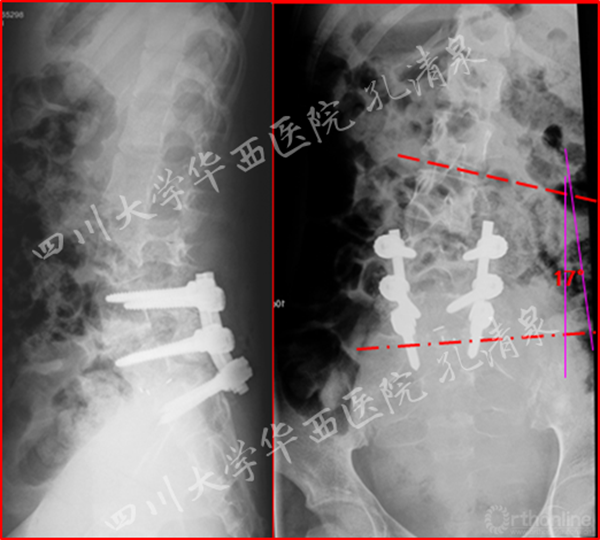

图4 术后复查 侧凸残留17°

图5 术后矢状面CT重建显示复位情况良好

治疗:经后路腰4-骶1固定、腰5滑脱复位、椎管减压、植骨融合术,术后患者左腿疼痛消失,术后复查侧凸残留17°,术后6月复查发现侧凸自发的减轻,术后两年复查时侧凸得到完全的矫正。